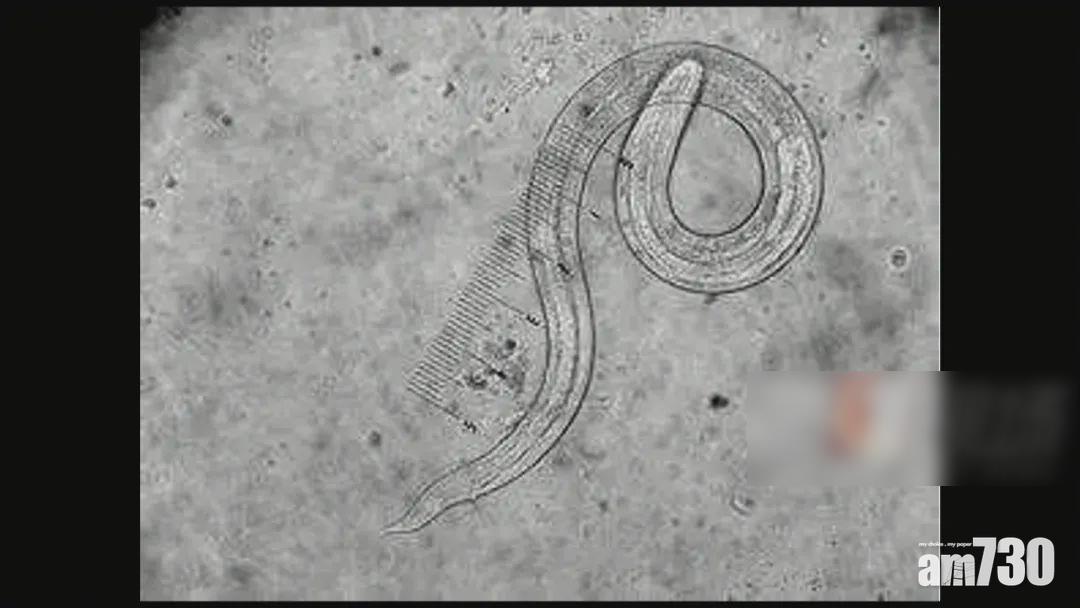

廣州管圓線蟲。(互聯網)

內地傳媒引述男子指,自己有些不好的習慣,例如從小到大都喝生水,無論是自來水、井水還是河水,都不煮沸直接喝。報道又指出,廣州管圓線蟲最終宿主是老鼠,中間宿主包括褐雲瑪瑙螺、福壽螺、蛞蝓(鼻涕蟲)等,而人類是「非正常宿主」,若食用未煮熟、藏有涉事幼蟲的螺肉,或者飲用有涉事幼蟲的生水等,幼蟲就會入侵人體各器官,引起相應症狀,如胸痛、腹痛、皮膚痛覺過敏、發燒及肢體癱瘓等。